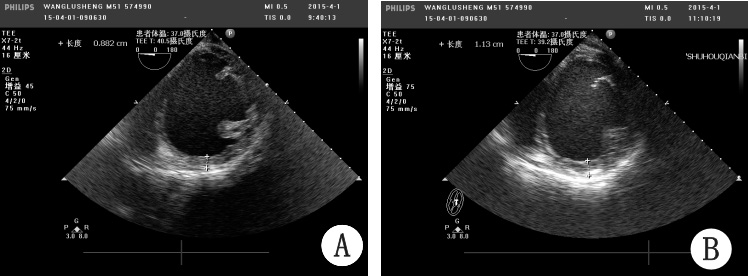

经过医院伦理委员会通过,患者及家属充分知情同意后,2015年4月1日在外科手术室行Algisyl可植入性水凝胶治疗。具体操作流程如下:(1)全身麻醉、气管插管;(2)由心脏大血管外科医生实施左侧肋间切口,暴露心脏;(3)确认左心室中间水平为注射部位,使用外科标记笔划一直线作为标记,注射点分布在距标记线约1 cm左右的两侧,避开可视的血管,每个注射点之间的距离1.5 cm左右(总注射针数取决于患者心脏大小,一般14~19点);(4)每个注射点注射0.3 mL Algisyl,持续缓慢的方式注射(大约0.1 mL/s);(5)闭合手术切口,手术结束。首次采用斜行进针和实时超声监控的方法见图 1和图 2。避免Algisyl进入血液,提高手术的安全性。术中、术后心电监护可见少量室性早搏,未发现持续性室速、室颤等恶性心律失常现象,无心脏骤停、过敏、栓塞等不良事件。术后患者胸闷气急等症状明显缓解,恢复良好,顺利出院,短期和远期疗效有待于进一步随访。

| A:注射前;B:注射后 图 2 患者术中实时心脏超声监控结果 Fig 2 Real-time ultrasonic monitoring |